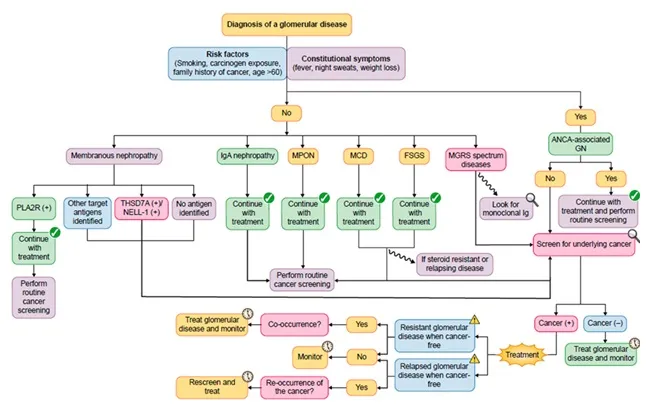

Segue esse Algoritmo e manda as duvidas pelo nosso whatsapp!

2. Quando e como investigar câncer em pacientes com GN?

3. Devo reavaliar câncer se o GN recidiva ou refratário ao tratamento?

5. Quando tratar com imunossupressor... ou focar no tumor?

Quando suspeitar fortemente de GN paraneoplásico?

GN recidivante ou refratário = pensar em câncer?

Sim. O artigo reforça que:

Como tratar?